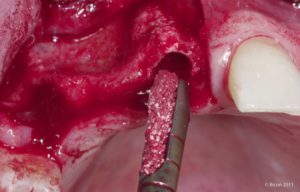

El sistema describe una técnica de fresado ultralenta, de 50 rpm como máximo (5, 17). Trabajar a esta velocidad elimina el riesgo de sobrecalentamiento del hueso, permite un mejor control manual, disminuye el estrés del operador y la fatiga del hueso tratado y además permite la recolección de hueso vivo, extraído por el mismo fresado. El hueso así obtenido es indudablemente el mejor relleno que se puede usar para cubrir posibles defectos ya que elimina el riesgo de rechazo, y en caso de necesidad incluso admite ser mezclado con otros biomateriales.

El incremento de temperatura es inferior a 4 ºC cuando se realiza un fresado ultralento (50 rpm), variación sin importancia desde el punto de vista de la viabilidad celular. La técnica resulta más precisa a esta velocidad, por lo que el lecho quirúrgico posee una mayor estabilidad inicial. El neoalvéolo labrado, al no ser lavado por ninguna solución irrigadora, estará impregnado de proteínas autólogas y, por lo tanto, en mejores condiciones biológicas para la osteointegración.